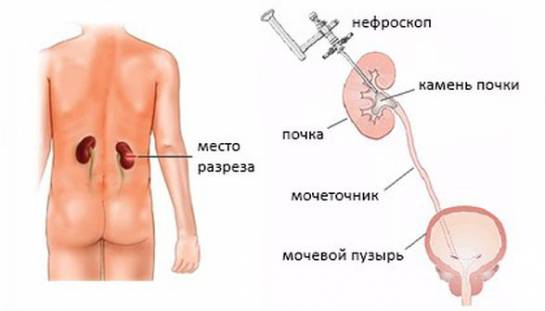

Интраренальная лоханка: рентгеновские снимки и примеры

Раздел: Фотоэссе